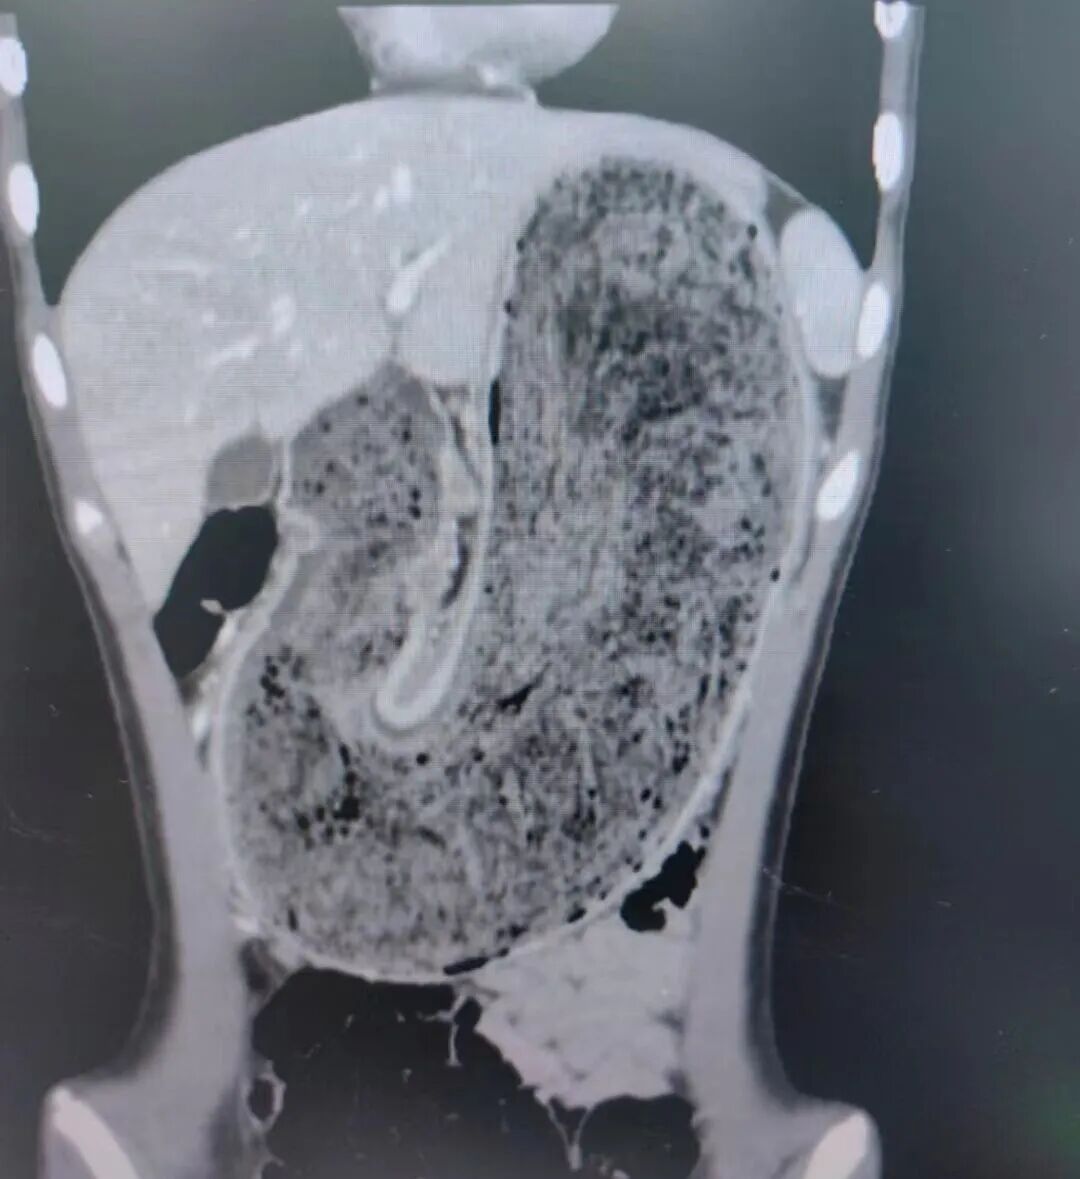

经检查,

医生发现她胃腔和肠管里

有大块的毛絮状结石。

几乎占据整个胃部,

不及时解决或将引发严重并发症。